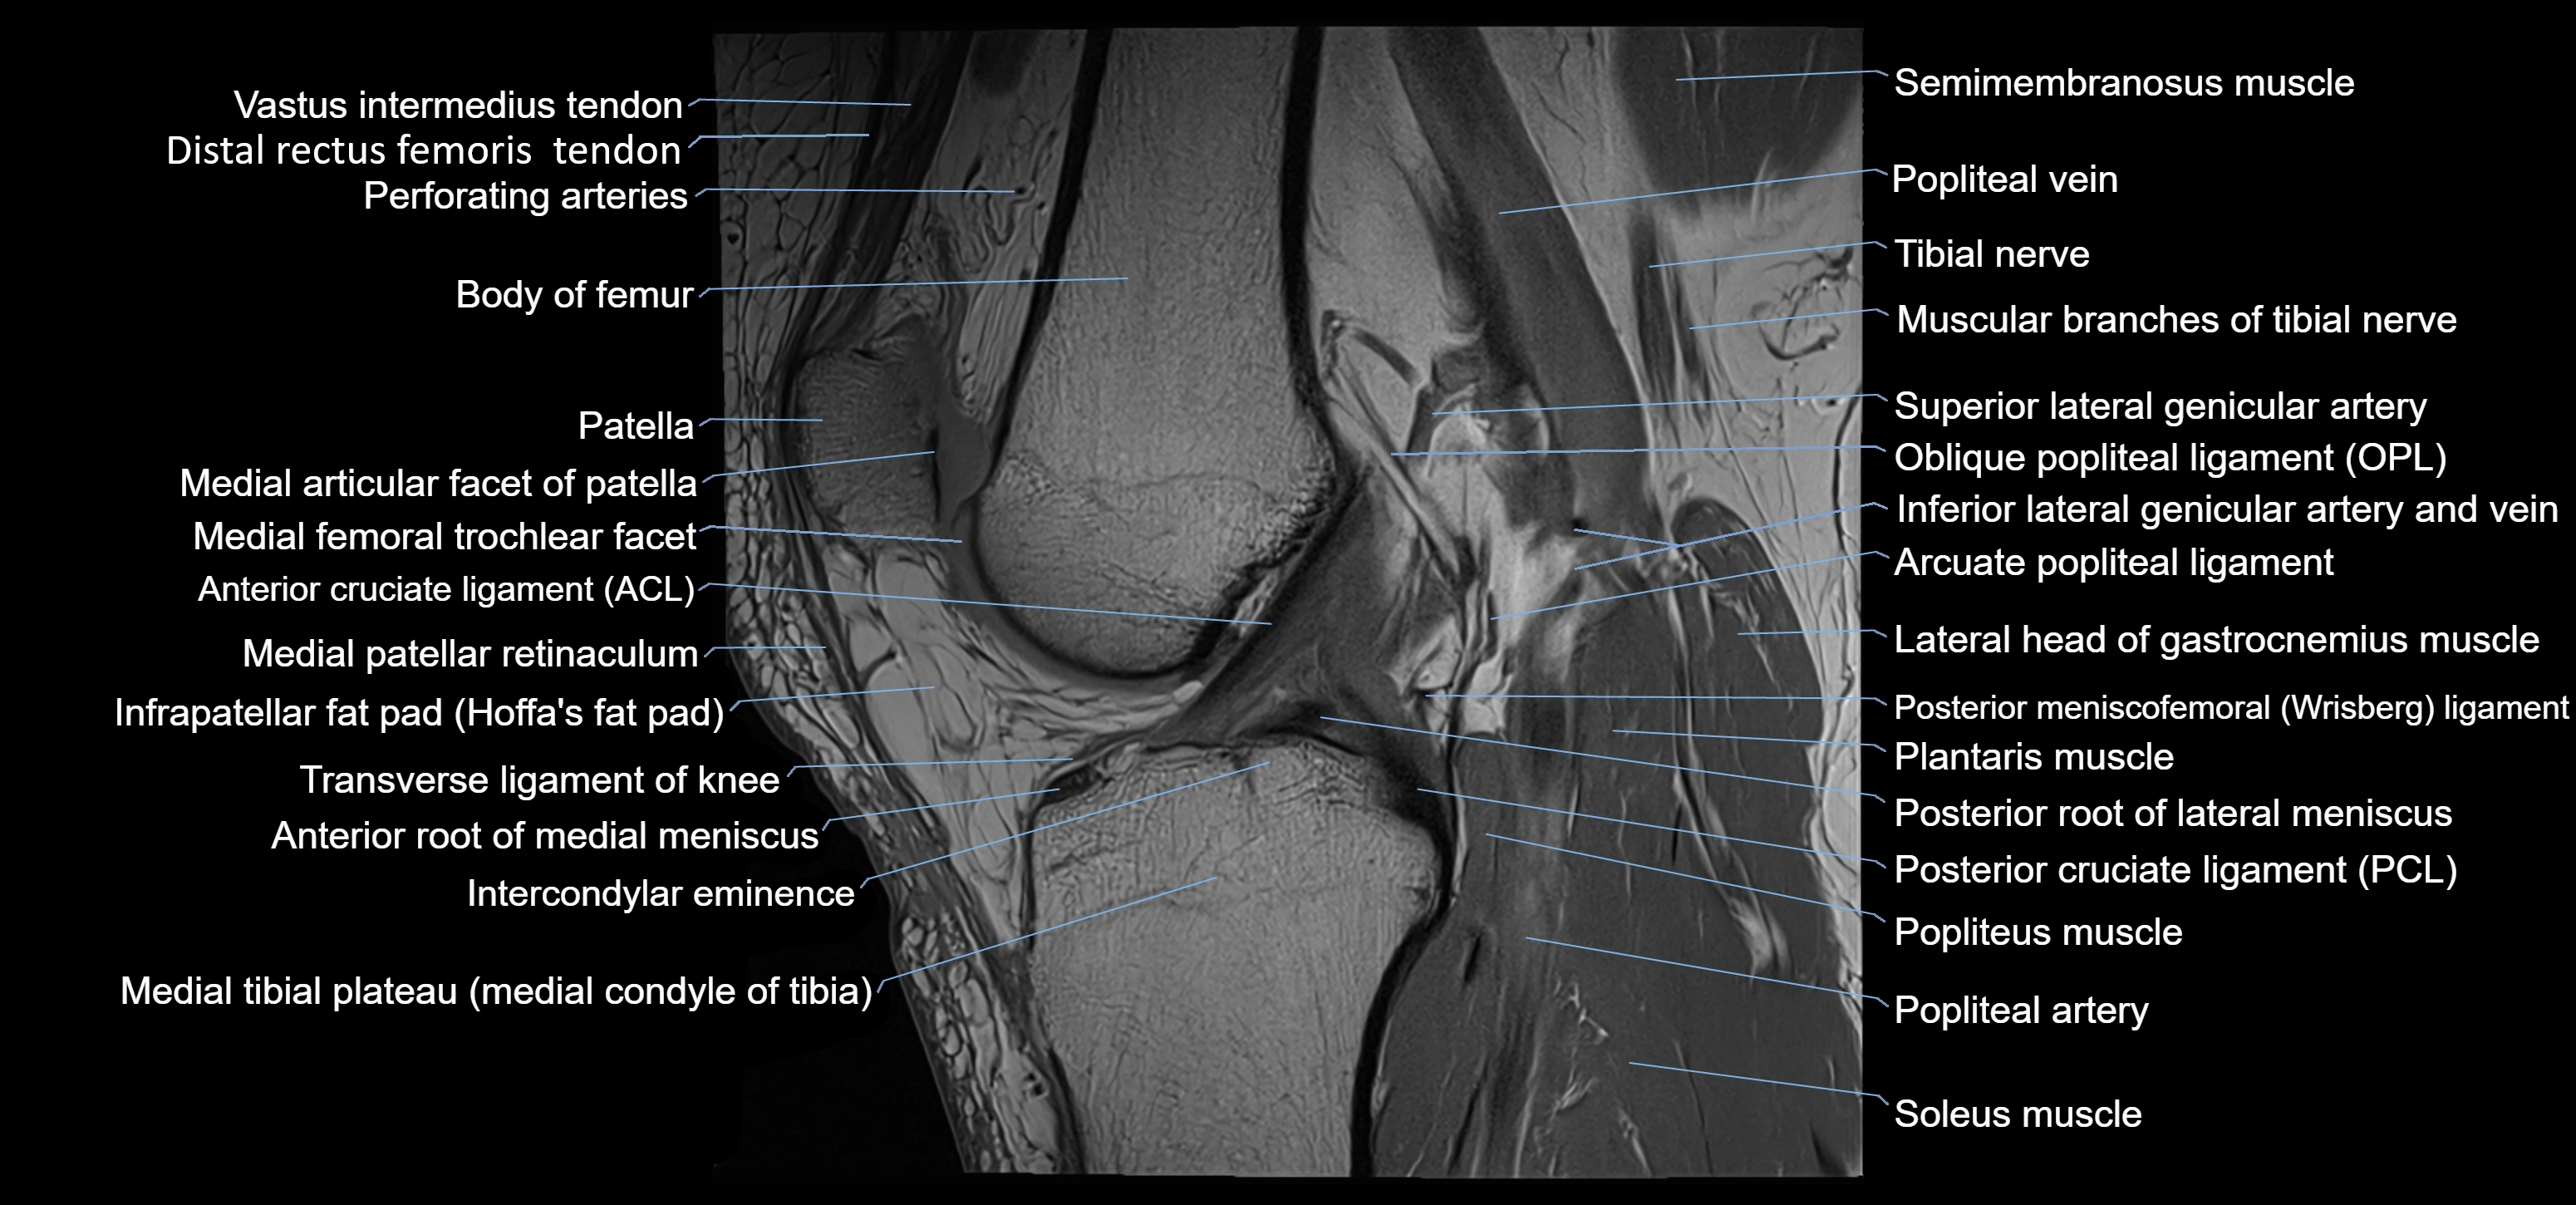

- Anterior cruciate ligament

- Anterior root of medial meniscus

- Arcuate popliteal ligament

- Body of medial meniscus

- Distal rectus femoris tendon

- Distal vastus intermedius tendon

- Intercondylar eminence

- Knee Joint

- Medial condyle of tibia

- Medial tibial plateau

- Oblique popliteal ligament

- Patella

- Patellar tendon (patellar ligament)

- Popliteal artery

- Popliteal vein

- Popliteus muscle

- Posterior cruciate ligament

- Posterior meniscofemoral ligament

- Posterior root of lateral meniscus

- Soleus muscle

- Superior lateral genicular artery

- Tibial nerve

- Transverse ligament of knee